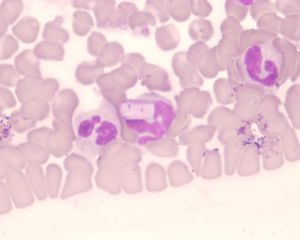

Hepatozoon canis (Hund)

Die hier gebildeten Merozoiten dringen in die Leukozyten ein und differenzieren sich zu den Gamonten. Der Endwirt, die Zecke, nimmt die Gamonten bei der Blutmahlzeit auf, und im Darm der Zecke erfolgt die Gamogonie. Es entstehen die beweglichen Zygoten, die den Darm der Zecke verlassen und in das Haemozoel einwandern. Hier findet die Sporogonie statt und es werden Oozysten mit je 16 infektiösen Sporozoiten gebildet. Die Infektion mit H.canis erfolgt durch das Zerbeißen oder Verschlucken infizierter Zecken.